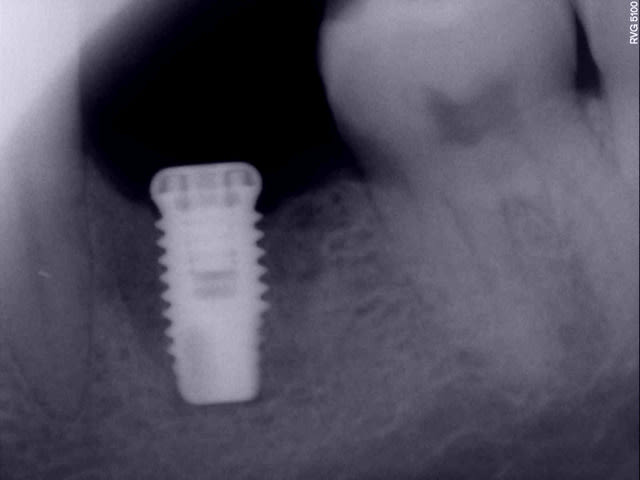

Une perte osseuse non infectée n'est pas une périimplantite et elle se stabilise à un certain niveau lorsque le système est en bio-équilibre.

Ici, il est dommage que l'implant soit un peu court, ce qui peut entrainer sa perte par surcharge.

Je ne pense pas que ce soit une périimplantite et le tabac n’est pas la cause de la perte osseuse mais un facteur aggravant.

bonsoir, ci dessous quelques réflexions personnelles sur cette péri-implantite

Par ailleurs, un axiom se pose effectivement en infra osseux d'1/2mm mini, et à priori, il y avait vraiment la place pour le faire. Les conséquences auraient été un peu "moindres" s'il avait été posé de cette manière. Maintenant, ça arrive à tout le monde de ne pas faire la pose parfaite, ça m'est arrivé à moi aussi évidemment.

Dans ton cas, si ton implant n'est pas mobile, je le garderai après curetage soigneux sous aide visuelle et décontamination par aeropolissage et bétadine, et ensuite, comblement et membrane avec suture sans tension et couverture AB.

Ce qui me chagrine dans une dépose, s'il est encore fixe bien sûr, c'est que tu risque d'aggraver la perte osseuse existante et de créer un cratère entre la 5 et la 7, ce qui va peut-être compliquer la maintenance paro après la pose de la couronne, ou l'esthétique de la couronne.